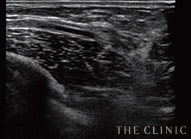

実際のエコー画像

吸引・除去後   しこりの消失を確認